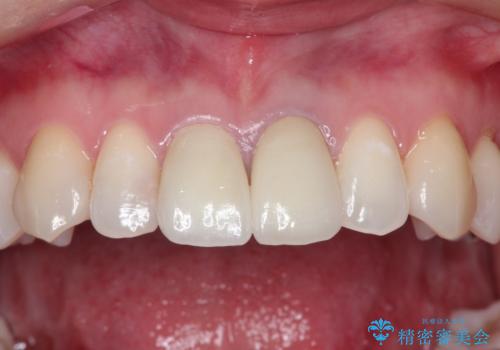

前歯の根元が黒い オールセラミッククラウンの装着による改善

かぶせ物と歯の境目の再設定を行い、適合の良いかぶせ物を装着することで、審美的に自然な状態に改善することができました。